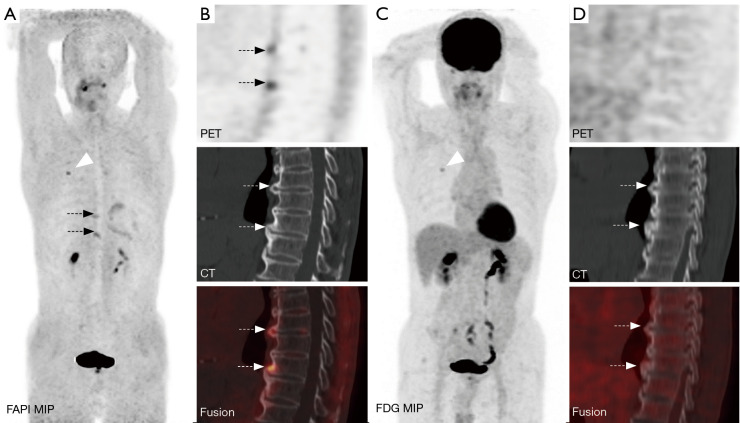

Background: Bone metastases of lung cancer typically indicate disease progression and poor prognosis. Early and accurate detection is crucial for staging, treatment planning, and prognostic evaluation. This study aimed to compare the diagnostic value of gallium 68-labeled fibroblast-activation protein inhibitor-04 ([68Ga]Ga-FAPI-04) and fluorine 18-labeled fluorodeoxyglucose ([18F]FDG) positron-emission tomography/computed tomography (PET/CT) imaging in detecting bone metastases in lung cancer.

Methods: A retrospective analysis was conducted on patients with pathologically confirmed lung cancer and clinically suspected bone metastases. These patients underwent both [68Ga]Ga-FAPI-04 and [18F]FDG PET/CT imaging. Initially, all patient images were visually evaluated, and the diagnostic efficacy of the two imaging methods was compared at both the patient and lesion levels for detecting bone metastases from lung cancer. Additionally, a semi-quantitative analysis was performed to compare the optimal maximum standardized uptake value (SUVmax) threshold and diagnostic efficacy of the two examinations for diagnosing benign and malignant bone lesions.

Results: A total of 25 lung cancer patients were included in the study, with nine confirmed cases and 133 lesions of bone metastases. At the patient level, there were no statistically significant differences in the detection rate, sensitivity, specificity, positive predictive value, negative predictive value, or accuracy between [68Ga]Ga-FAPI-04 and [18F]FDG PET/CT for identifying patients with bone metastases (P>0.05). At the lesion level, the detection rate, sensitivity, negative predictive value, and accuracy of [68Ga]Ga-FAPI-04 PET/CT for detecting bone metastases were higher than those of [18F]FDG PET/CT (81.37% vs. 57.14%, 98.50% vs. 69.17%, 88.24% vs. 34.92%, 90.68% vs. 70.81%), with statistically significant differences (P<0.01). The SUVmax of malignant bone lesions on both [68Ga]Ga-FAPI-04 and [18F]FDG PET/CT was significantly higher than those of benign bone lesions, with statistically significant differences (P<0.05). Moreover, the SUVmax of benign and malignant bone lesions on [68Ga]Ga-FAPI-04 PET/CT was significantly higher than those on [18F]FDG PET/CT, with statistically significant differences (P<0.01). In [68Ga]Ga-FAPI-04 and [18F]FDG PET/CT imaging, the area under the curves (AUCs) of SUVmax for diagnosing bone metastases were 0.856 and 0.724, respectively, with statistically significant differences (P<0.05); the optimal diagnostic thresholds were 5.38 and 3.77, respectively. The sensitivity, negative predictive value, and accuracy of SUVmax based on [68Ga]Ga-FAPI-04 PET/CT for diagnosing lung cancer bone metastases were higher than those based on [18F]FDG PET/CT (80.45% vs. 65.26%, 46.49% vs. 23.26%, 81.25% vs. 67.29%), with statistically significant differences (P<0.05).

Conclusions: Compared to [18F]FDG PET/CT, [68Ga]Ga-FAPI-04 PET/CT significantly improves the detection rate of lung cancer bone metastases at the lesion level. Additionally, [68Ga]Ga-FAPI-04 PET/CT offers superior image contrast and higher SUVmax, which also contribute to improving the accuracy of lung cancer bone metastasis diagnosis. This allows for more accurate staging of patients, enabling precise individualized treatment and improving patient prognosis.